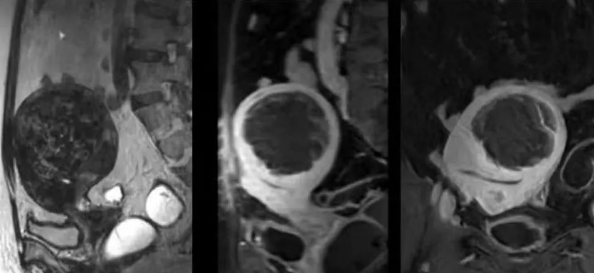

陳寶瑩主任首先給祝女士進(jìn)行了詳細(xì)的盆腔磁共振評(píng)估,發(fā)現(xiàn)子宮肌瘤比較大,直徑七公分,類型和位置都適合做磁波刀治療。陳寶瑩主任立即為她制定了個(gè)性化治療方案,并為她完成幾項(xiàng)術(shù)前檢查。

治療當(dāng)天,為緩解祝女士的緊張心情,陳寶瑩主任和她進(jìn)行了充分溝通。術(shù)前準(zhǔn)備就緒后,治療正式開始了。治療過(guò)程中,患者全程清醒,可以及時(shí)反饋治療感受。醫(yī)生也即時(shí)調(diào)整,確保整個(gè)治療安全有效,兩小時(shí)后治療順利結(jié)束,患者體驗(yàn)度好。即時(shí)評(píng)估發(fā)現(xiàn)7公分的子宮肌瘤被消融掉80%,達(dá)到了預(yù)期目標(biāo)。祝女士觀察一個(gè)小時(shí)后,沒(méi)有什么不舒服即回家了。